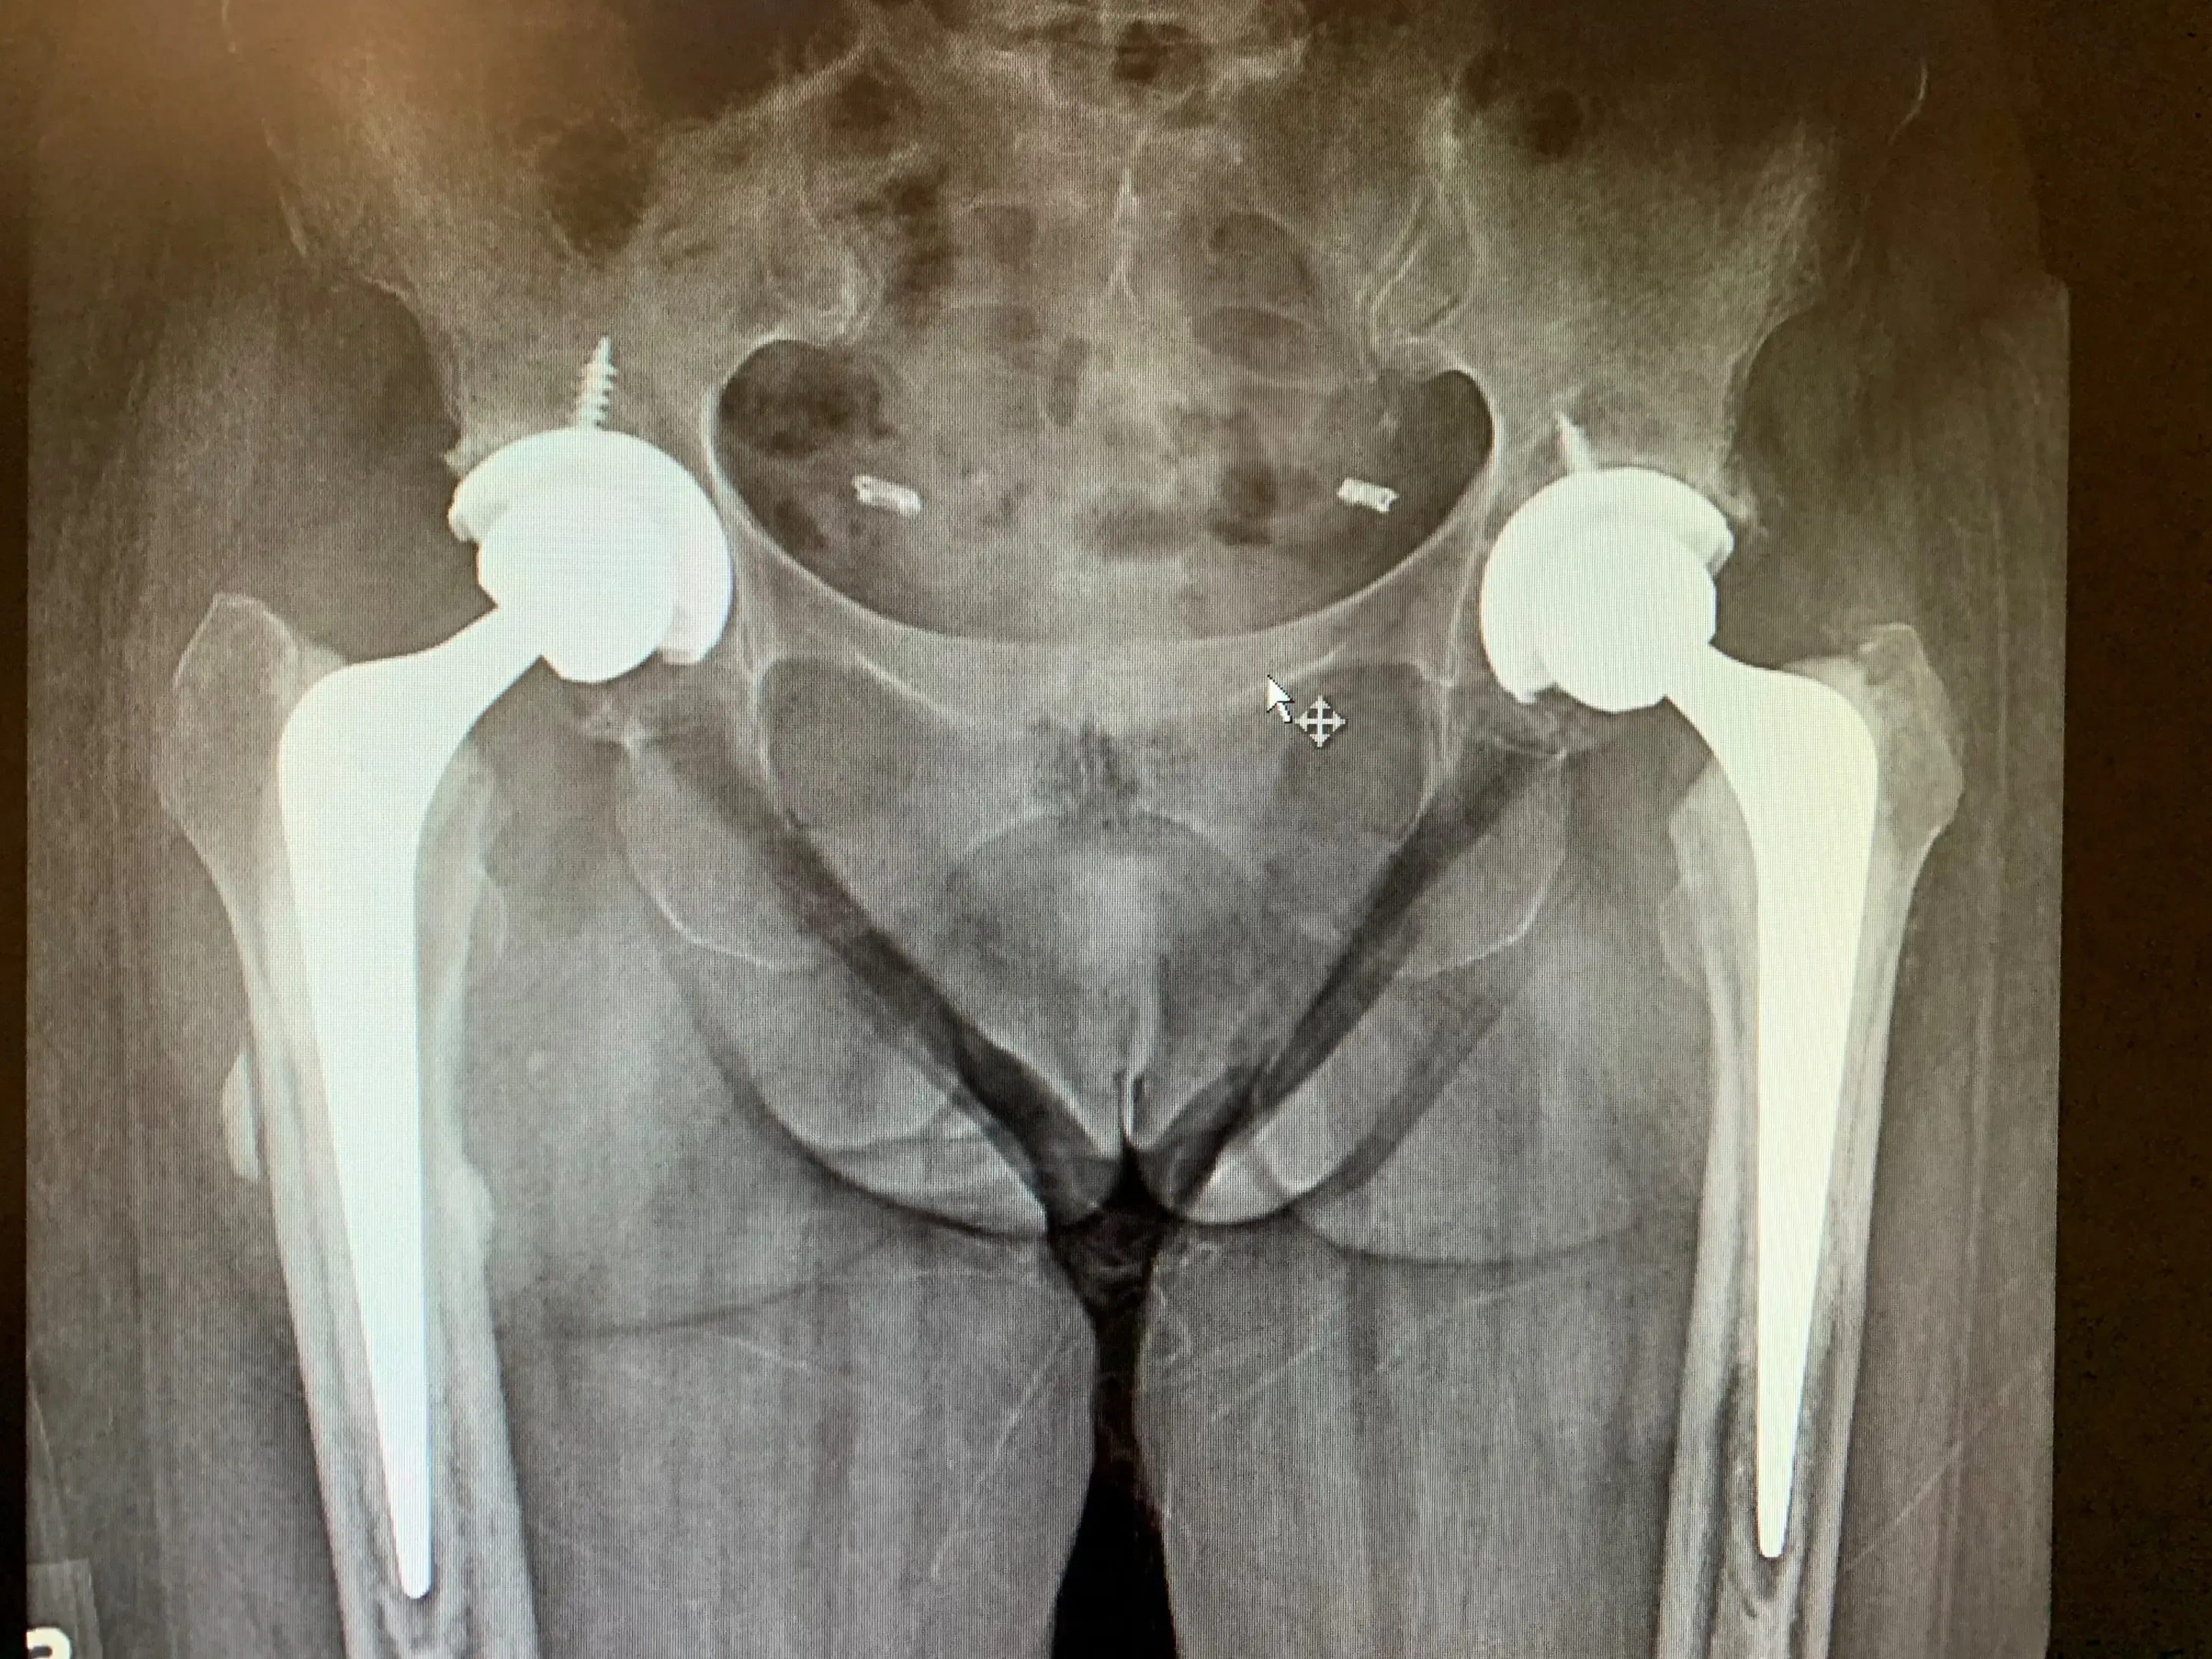

Full assessment of Mrs. CM including examination and radiographs revealed bilateral hip osteoarthritis of moderate severity. Her hip examination was unremarkable, with a remarkably good range of motion considering the level of arthritis she suffered from.

We explained that, should she would be a candidate for simultaneous bilateral anterior Total Hip Arthroplasty given her lack of medical comorbidities and her essentially equal severity of arthritis in each hip. She was agreeable to this, and provided informed consent.

We performed her anterior approach hip replacements on a special table that enable us to manipulate each leg independently. We completed her left hip replacement before starting the right side, but all under the same general anaesthesia.

Post-op